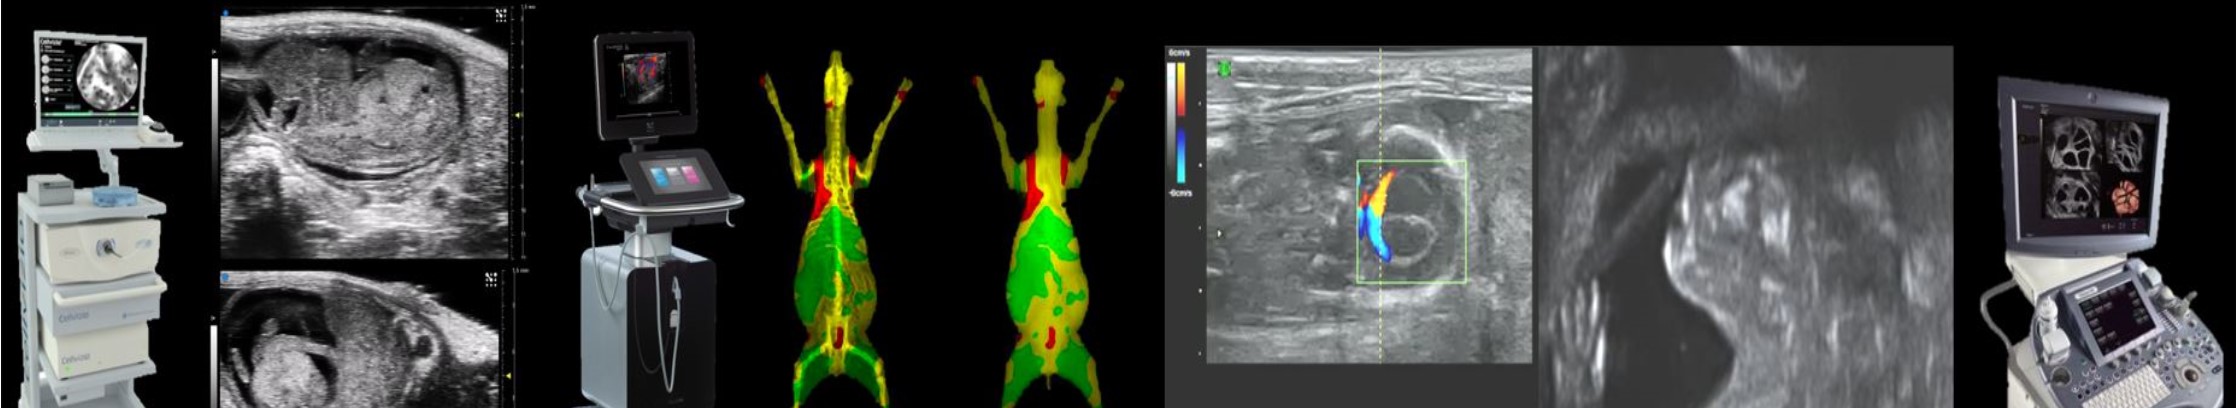

Within this ISC, the CIMA platform (Animal Surgery and Medical Imaging) provides various in vivo imaging techniques using IDXA X-rays (osteodensitometry, quantification of fat and lean masses), Cellvizio fibrous confocal endomicroscopy (488 nm in vivo cell imaging) and ultrasound (conventional ultrasound and micro-ultrasound or high-resolution ultrasound).